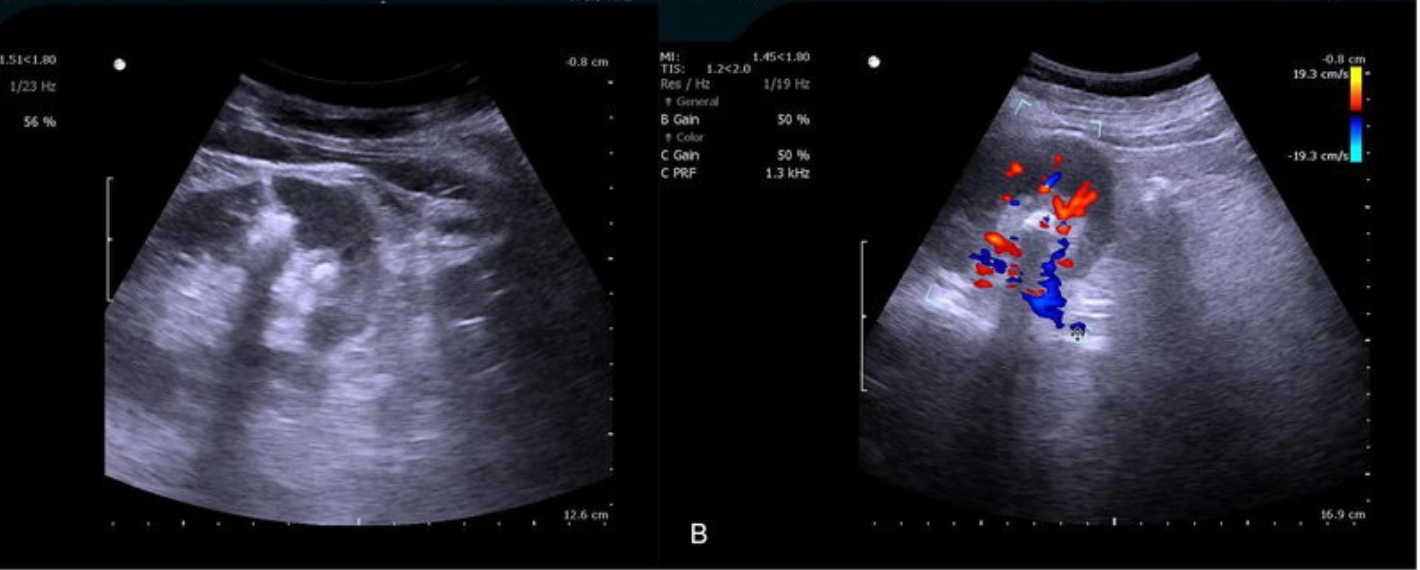

Men’s health assessments are crucial for proactive healthcare. Our clinic provides a comprehensive range of scans tailored to men’s specific needs like abdominal, urinary tract, and transabdominal prostate scans. We also offer combined abdominal and urinary tract assessments for a comprehensive evaluation. Specialized scans include groin ultrasounds for hernias, lymph nodes, and soft tissue assessments. Testicular ultrasounds assess testicular health and abdominal aortic aneurysm (AAA) assessments screen for potentially life-threatening conditions. These assessments are crucial for proactive healthcare and help identify potential health issues early on.